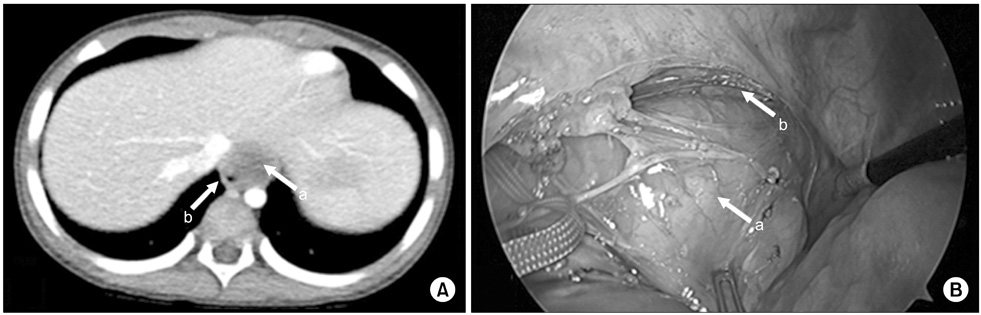

Fig. 4

Esophageal duplication cyst of superior mediastinum. (A) There was a mass situated at just front of upper esophagus on neck MRI (2.5×2.2×4.5-cm-sized mass). (B) There was a mass at the front and right of the esophagus. Arrows: a, esophageal duplication cyst; b, true esophagus.

Fig. 4 Esophageal duplication cyst of superior mediastinum. (A) There was a mass situated at just front of upper esophagus on neck MRI (2.5×2.2×4.5-cm-sized mass). (B) There was a mass at the front and right of the esophagus. Arrows: a, esophageal duplication cyst; b, true esophagus.